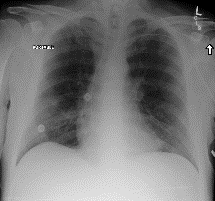

Among various medical imaging tools, chest radiographs are the most important and widely used diagnostic tool for detection of thoracic pathologies. Research is being carried out in order to propose robust automatic diagnostic tool for detection of pathologies from chest radiographs. Artificial Intelligence techniques especially deep learning methodologies have found to be giving promising results in automating the field of medicine. Lot of research has been done for automatic and fast detection of pneumothorax from chest radiographs while proposing several frameworks based on artificial intelligence and machine learning techniques. This study summarizes the existing literature for the automatic detection of pneumothorax from chest x-rays along with describing the available chest radiographs datasets. The comparative analysis of the literature is also provided in terms of goodness. Limitations of the existing literature along with the research gaps is also given for further investigation. The paper provides a brief overview of the present work for pneumothorax detection for helping the researchers in selection of optimal approach for future research.